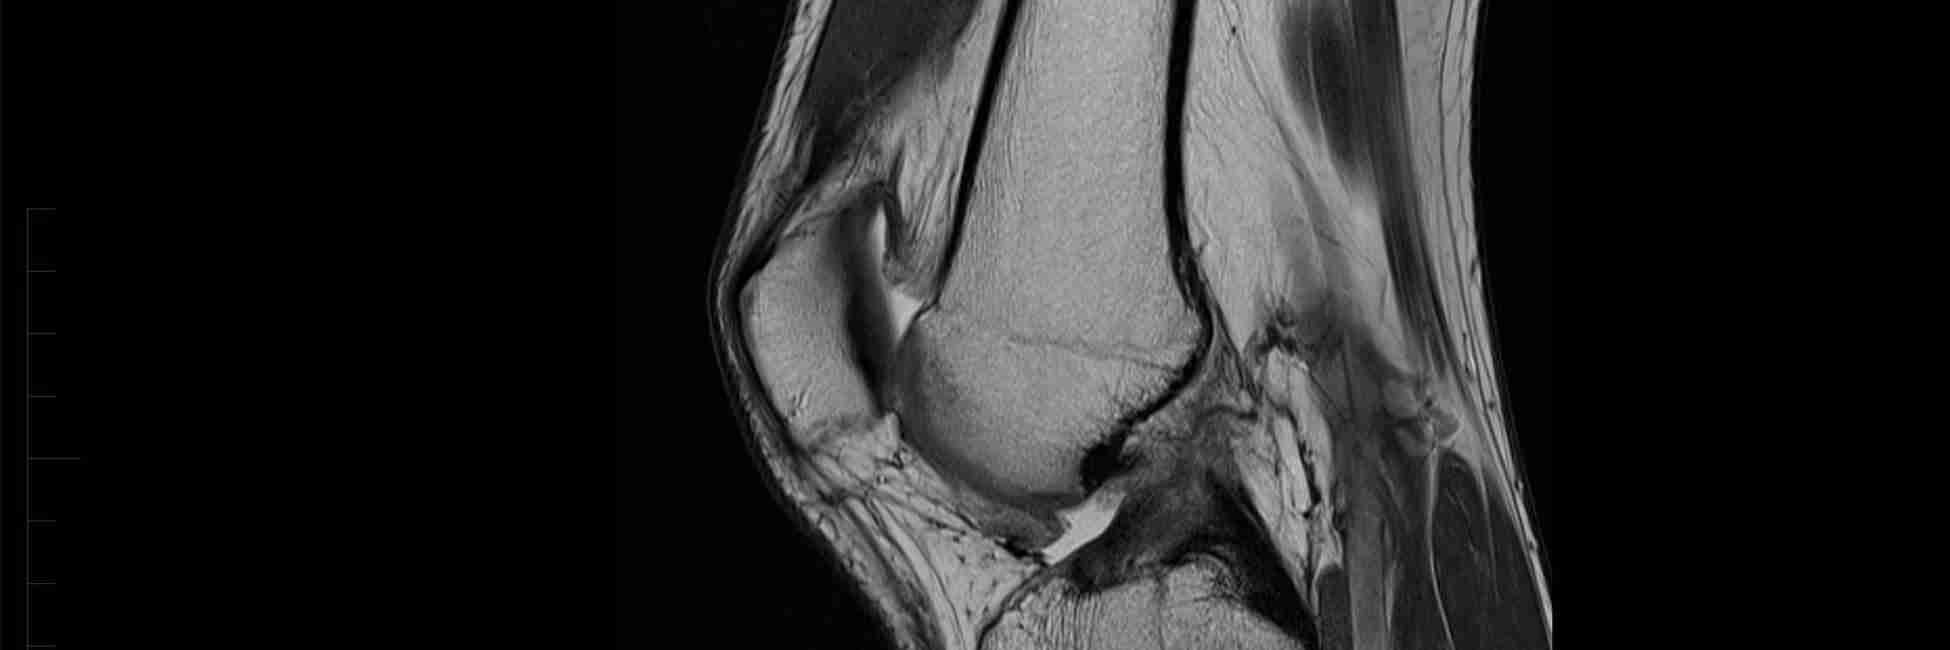

When MRI scans don’t give us the answer

Magnetic resonance imaging or the ‘MRI’ is often the go to by many in the medical world given it’s name as the ‘gold standard’ in detecting muscle, ligament, bone, and cancerous structures.  MRI, along with x-rays, ultrasounds, bone scans, CT …